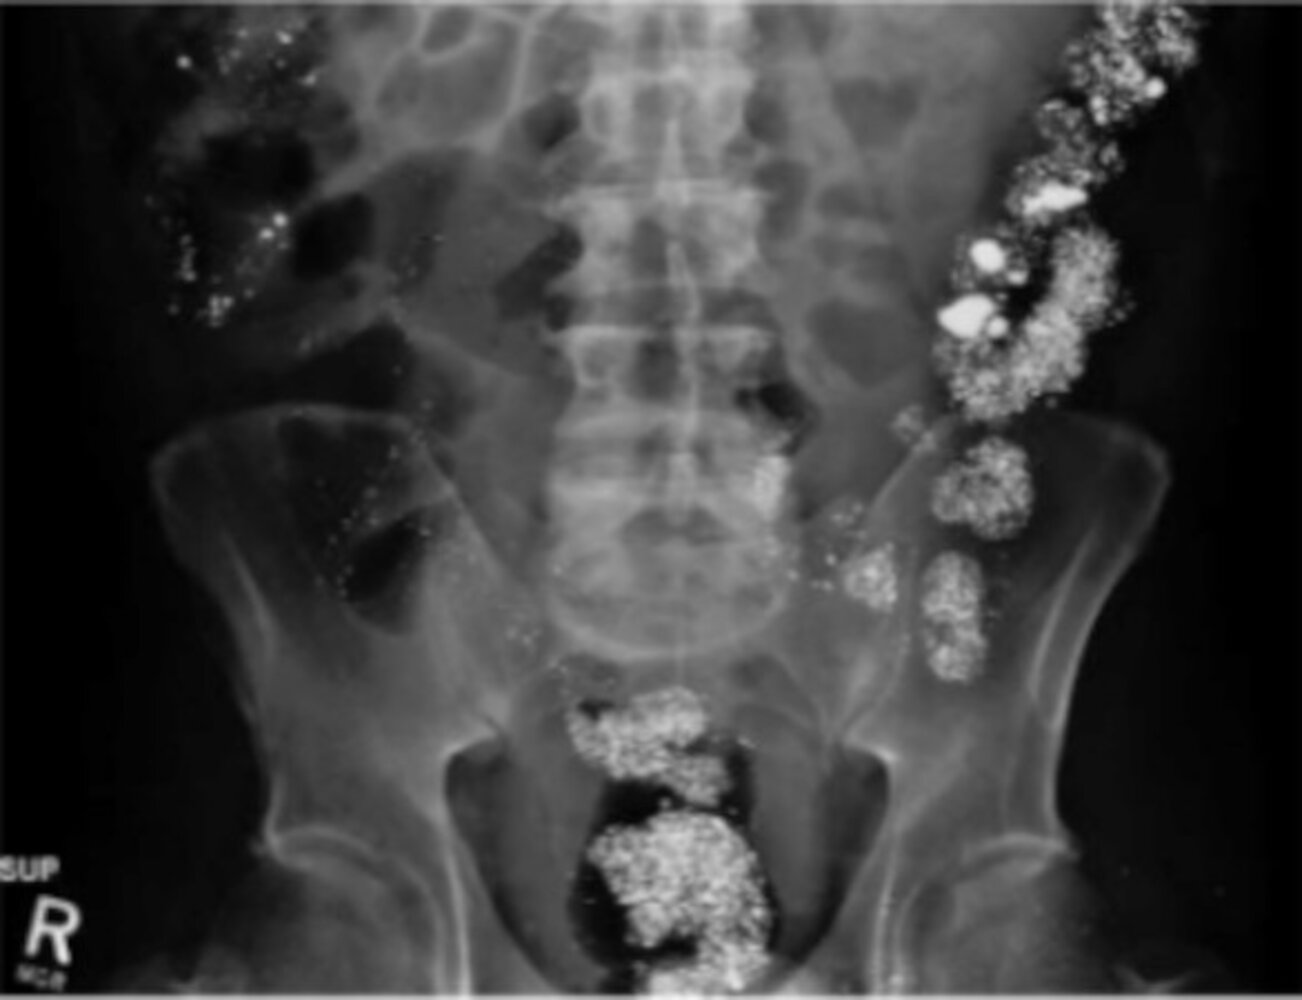

• X-ray or CT abdomen for ingestion of select radiopaque substances, such as: [22]

• Heavy metals (e.g., iron, lead, arsenic, mercury) [20]

• Packets containing substances such as opiates or cocaine [2]

• Chloral hydrate

• Phenothiazines

• Numerous sustained-release or enteric-coated substances

• Numerous industrial solvents (e.g., carbon tetrachloride)

To remember foreign substances with a radiopaque appearance on abdominal radiography, think of CHIPES: Chloral hydrate, Heavy metals, Iodides, Phenothiazines, Enteric-coated or sustained-release substances, and Solvents. [22]